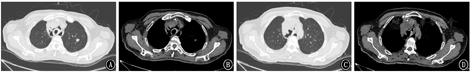

2018年5月23日复查胸部CT提示:淋巴瘤治疗后,气管瘘、纵隔瘘;纵隔、右侧锁骨上窝多发肿大淋巴结,双肺多发结节,脾脏占位,符合淋巴瘤,部分较前减小;双肺感染较前加重,双肺下叶膨胀不全;新增双侧胸腔积液;心包少量积液,较前相仿(图2)。2018月5月25日支气管镜见气道内弥漫白斑、黏膜糜烂,气管中段见巨型气管-纵隔瘘,左主支气管见3个瘘口,右上叶见1个瘘口(图3)。患者治疗过程中新发气管、支气管-纵隔瘘,考虑为原淋巴瘤浸润,累及纵隔及邻近的气管、支气管;化疗后,肿瘤组织消减,导致气管、支气管与纵隔间出现相通的窦道。患者气道弥漫性糜烂、多发巨型瘘口,难以自行愈合。目前气道内介入治疗方法,如气道支架、封堵器等不能解决瘘口问题,且支架、封堵器等机械压迫可能使原有气管/支气管瘘扩大。考虑患者气管/支气管-纵隔瘘虽存在,但纵隔内气体尚未引起心脏和纵隔大血管压迫;且瘘口未与食道相通,未引起难治性肺部感染等危及生命情况,决定采取保守治疗方式,继续予抗感染(产气肠杆菌和放线菌)及对症支持治疗。患者症状好转于2018年6月5日出院。但患者因个人因素,放弃进一步治疗,并于出院后2个月去世。